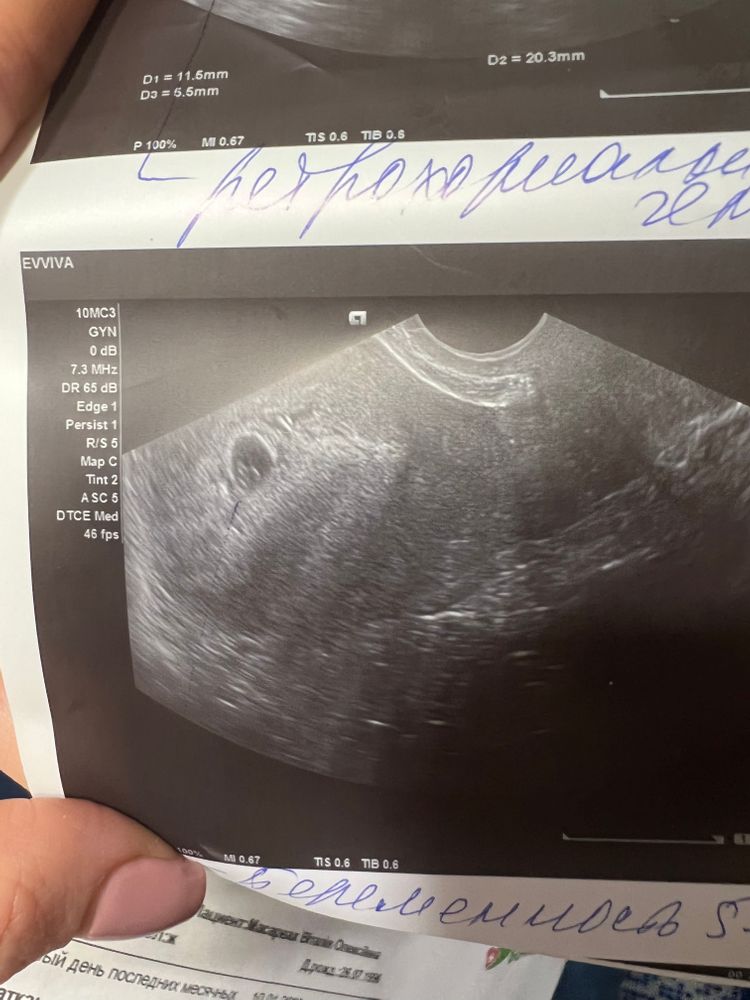

Поехала сегодня сделала узи , там все соответствует сроку 5-6недель пя 11-12мм

узист мне попалась максимально молчаливая и медленная ,по просила ее услышать сердечко она сказала нельзя на раних сроках .Показала мне на маниторе видно прям пя и в нем эмбриончик и прям пульсацию четка .Она написала ПЯ 11-12мм жм+. и все .Еще очень большая гематома (я на клексане ) (😭